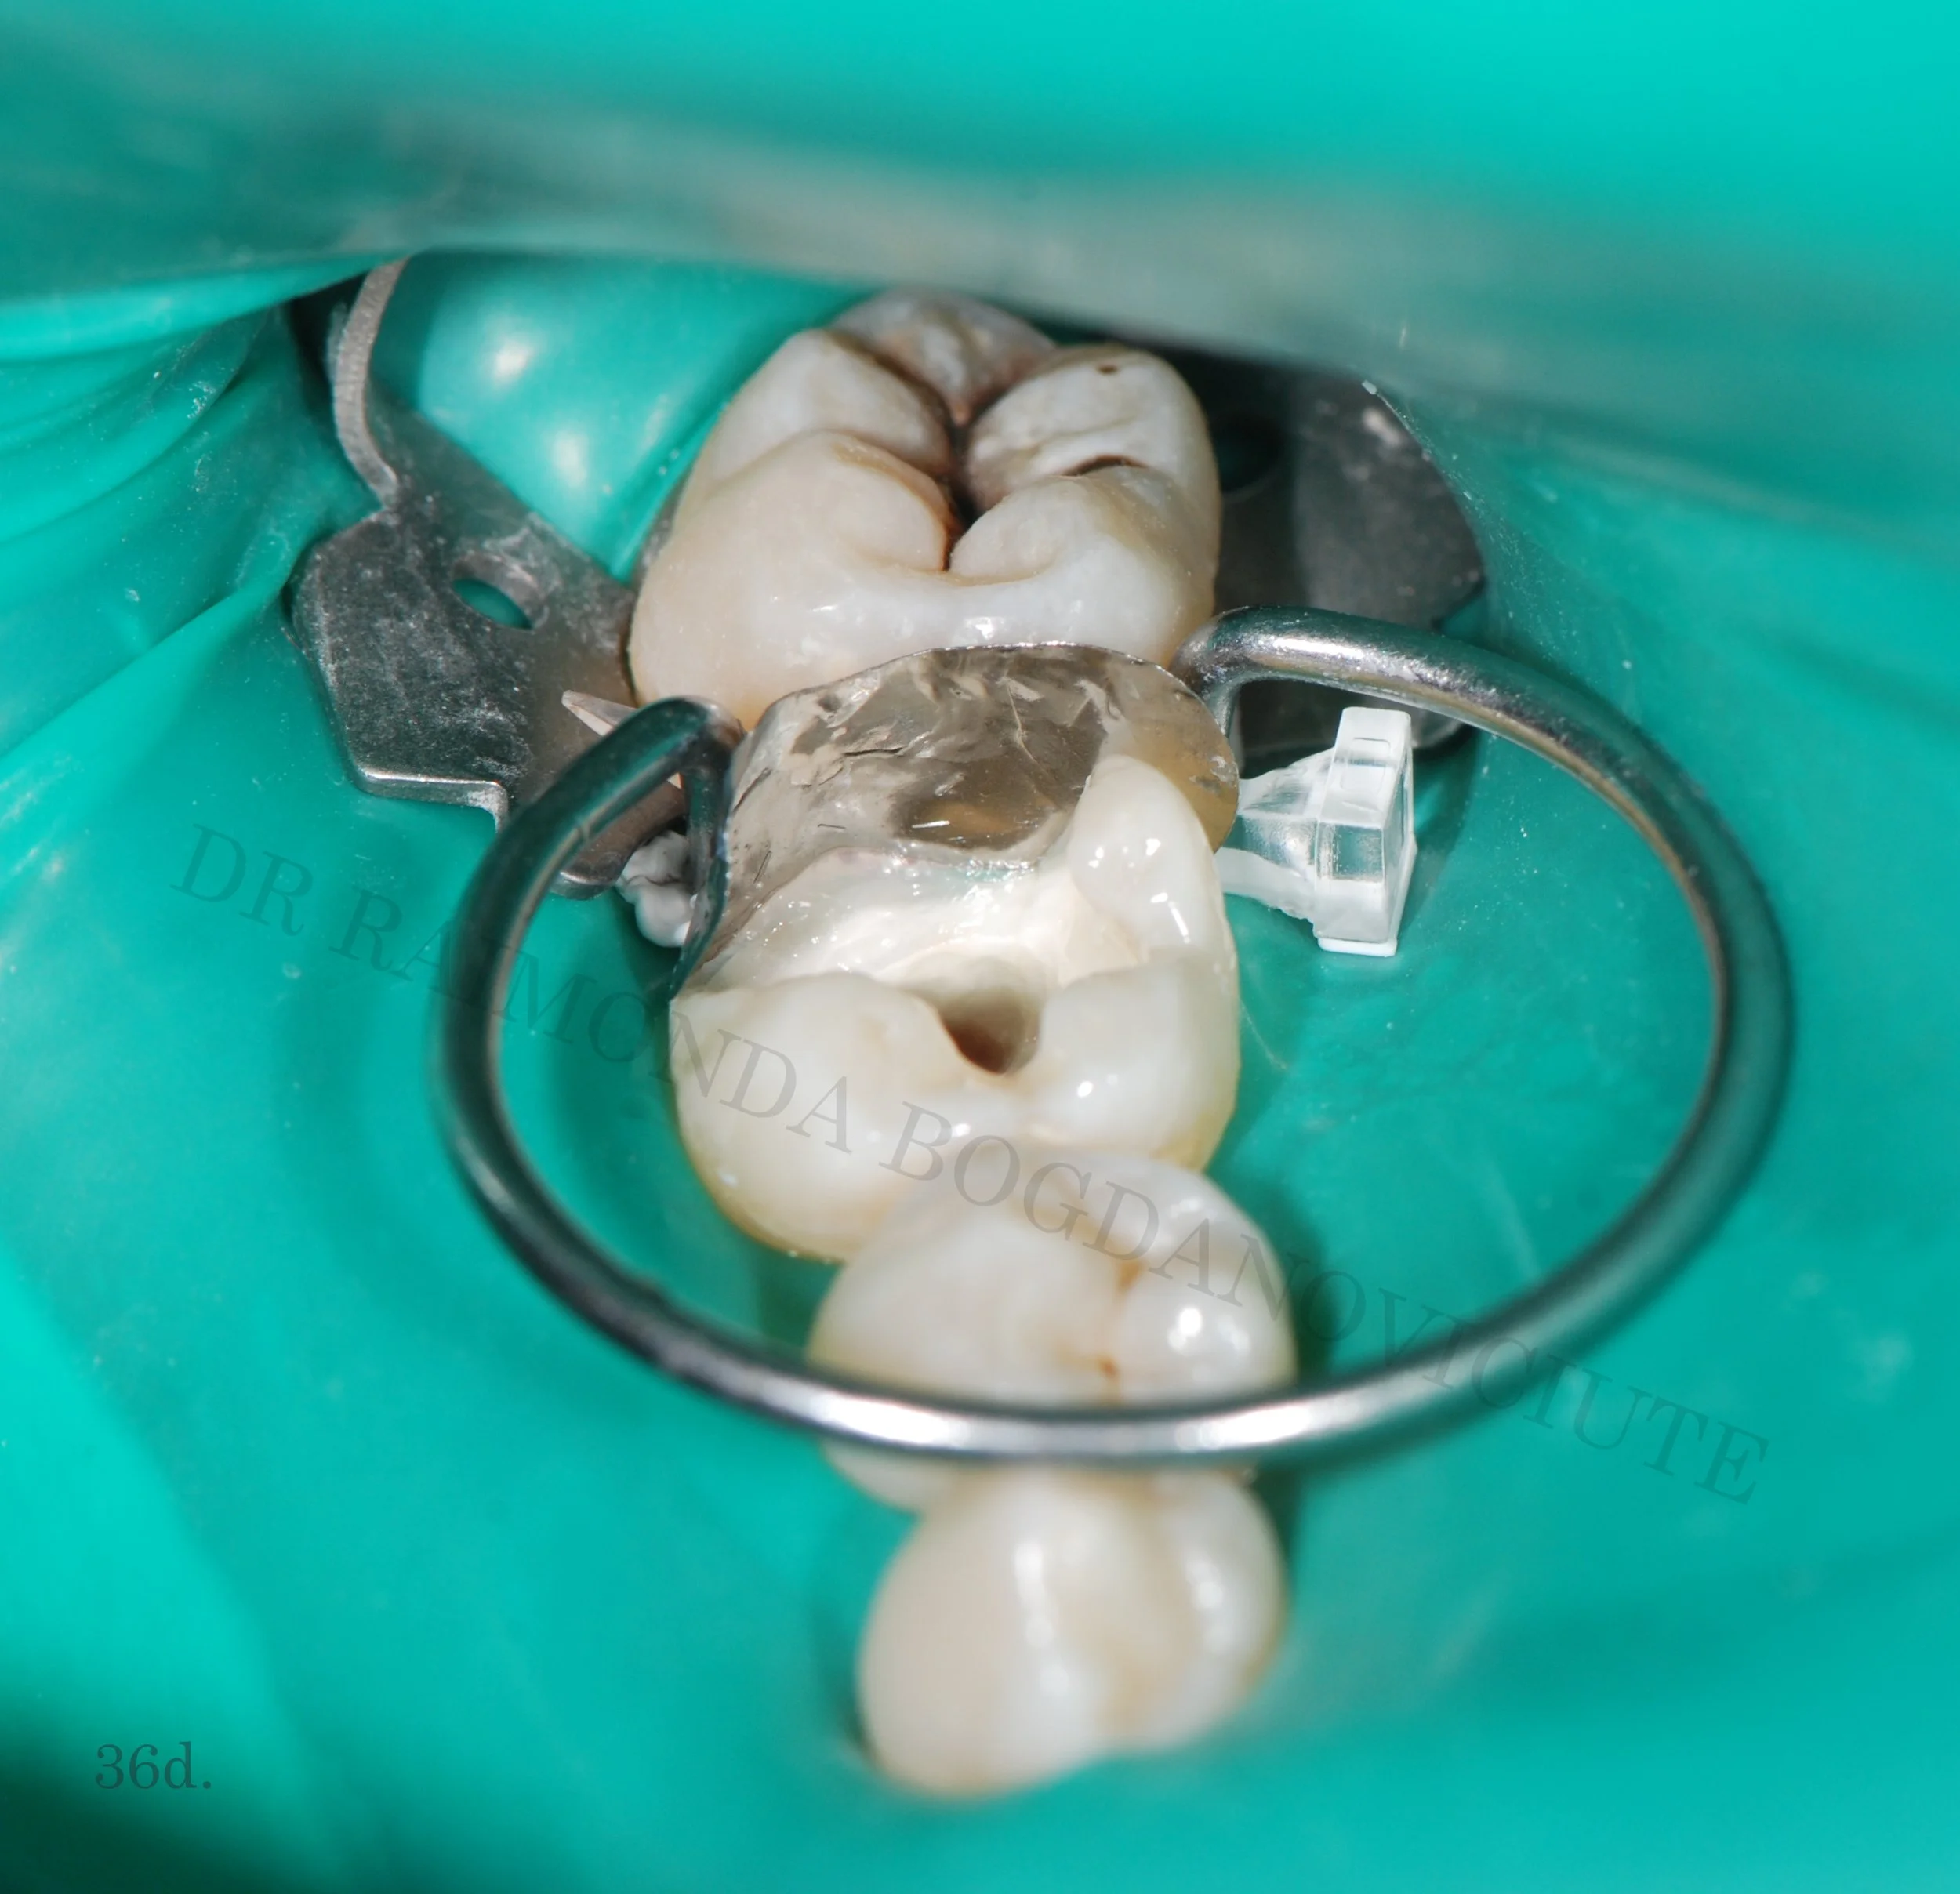

Functional Restorations

These are dental reconstructions that precisely rebuild lost dental tissue and returns full functionality for the teeth.

What is a functional restoration?

A functional restoration is any small or big dental reconstruction that re-creates lost dental anatomy and function. Every single cusp, ridge or groove on the surface of the tooth has a particular function and participates in chewing. Wrong reconstruction can lead to different negative consequences and even affect your overall health - poor mastication, tooth fracture, tooth pain, malposition of teeth, gingivitis, periodontitis, bone loss, headaches and many more.

Better than before

Correctly performed functional restoration following strict protocols guarantees long-lasting excellent results for plenty of years avoiding any of those negative oral health issues, strengthening your teeth and improving your mastication.

All our fillings from the smallest to the biggest one are performed in this way.

Functional restoration is not just a filling - it is a treatment based on thorough analysis of your bite, masticatory system, your habits, and performed following strict protocols of reconstructing correct teeth anatomy.